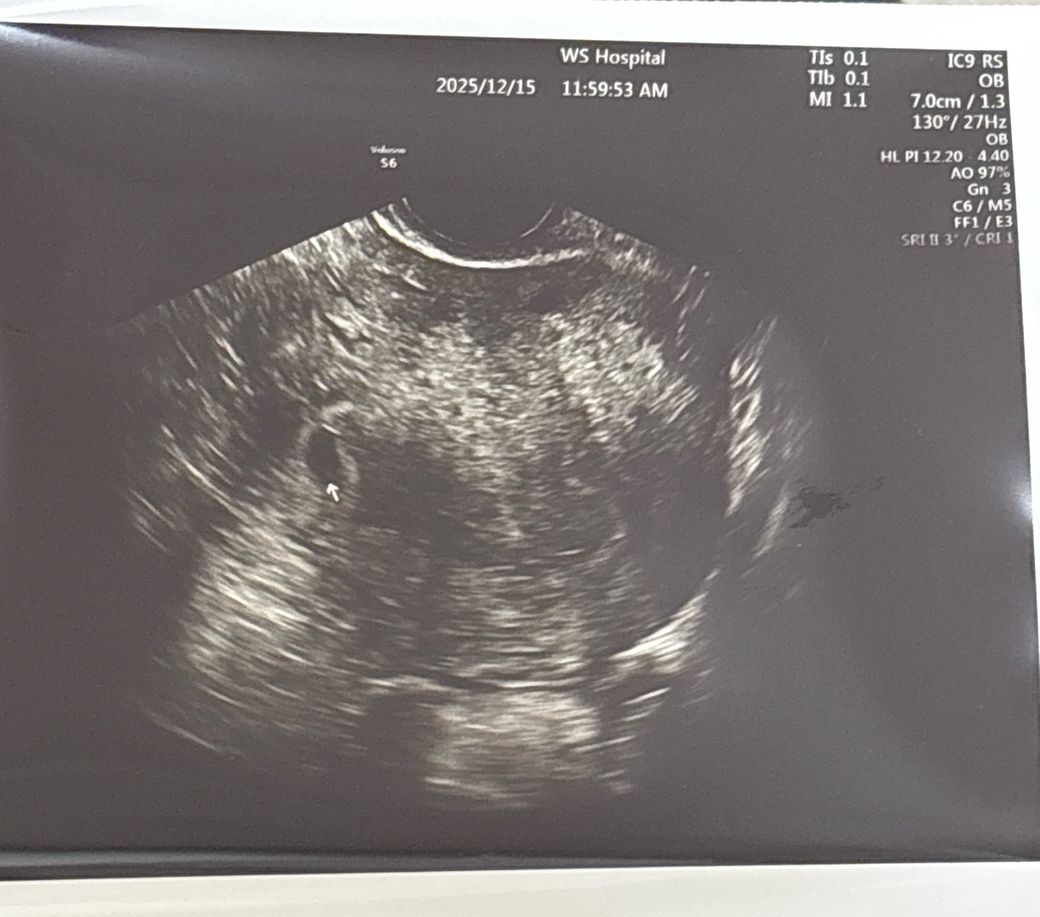

5주초반이라고하셨고 아기집안에 난황이 살짝보인다고했고 1cm조금 안된다고 하셨어요

근데 나팔관쪽에 가깝게 자리위치해있다고 안쪽으로 옮겨져야한다는데 괜찮을까요???

5주 초반에 아기집 약 1cm 미만, 난황이 보이는 것은 시기상 적절한 소견입니다. 배란이 빠르고 착상이 늦었다면 주수 대비 작게 보이는 것도 충분히 설명됩니다. 12/24에 심장소리 확인을 계획한 것도 표준적인 추적 일정입니다.

“나팔관 쪽에 가깝다”는 표현은 자궁 내에서도 한쪽 벽이나 하부 쪽에 위치해 보인다는 의미인 경우가 많고, 이 시기에는 자궁이 커지면서 상대적으로 중앙 쪽으로 위치가 바뀌는 경우가 흔합니다. 자궁외임신이 의심될 상황이었다면 바로 경고나 추가 검사 지시가 나왔을 가능성이 큽니다.

다만 다음 진료에서 아기집이 자궁 내에서 정상적으로 커지고 심박이 확인되는지가 가장 중요합니다. 복통, 한쪽 심한 통증, 출혈이 동반되면 즉시 진료는 필요합니다.